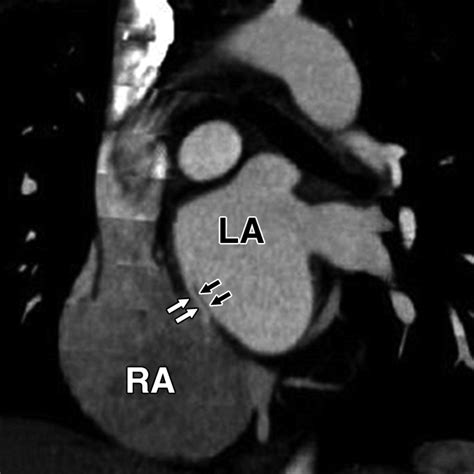

2408×2614

cvcasejournal.com

Three-dimensional Transesophageal Echocardio…

ajronline.org

ECG-Gated Cardiac CT Angiography Using 64-MDCT for …